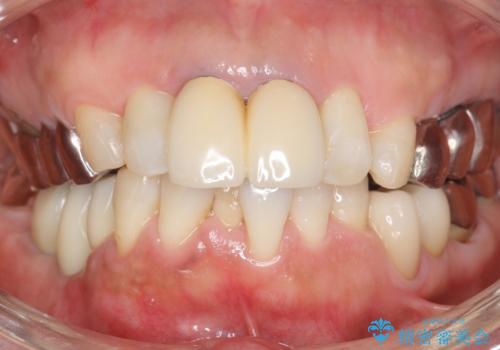

骨が薄く他院でインプラントできないと言われた 50代女性

- 奥歯のインプラントをご希望され、来院された患者様です。

骨が薄いため、他院ではインプラントできないと言われたとの事でした。

精査したところ、右下4の根尖病変及び右下5の欠損を認め、右下6は残根となり保存不可能な状態でした。

保存不可能な歯を抜去後、インプラント治療と根管治療を行いました。

奥歯でしっかり咬むことができるようになり、大変喜んで頂けました。

クラウンの種類:オールセラミッククラウン ベレッツァ